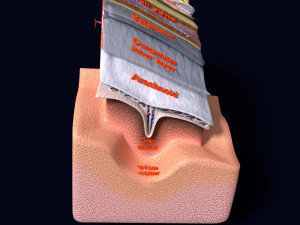

A blend model of brain along with its covering layers (meninges), skull bone and scalp labelled in detail and anatomically precise. The parts depicted are white, gray, pia, arachnoid, dura, bone, skin, fat, aponeurosis, periosteum, falx cerebri and more.

The material is high resolution image textures and normal maps based on non overlapping UVs. The texture and normal maps are packed with the blend file itself.